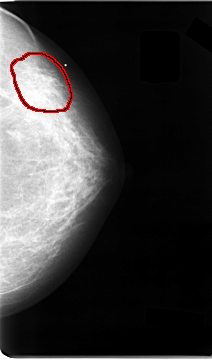

C_0026_1.LEFT_CC

LEFT_CC LINES 4672 PIXELS_PER_LINE 2744 BITS_PER_PIXEL 12 RESOLUTION 50 OVERLAY

FILE: C_0026_1.LEFT_CC.OVERLAY

TOTAL_ABNORMALITIES 1

ABNORMALITY 1

LESION_TYPE CALCIFICATION TYPE AMORPHOUS DISTRIBUTION CLUSTERED

LESION_TYPE MASS SHAPE ARCHITECTURAL_DISTORTION MARGINS ILL_DEFINED

ASSESSMENT 4

SUBTLETY 2

PATHOLOGY MALIGNANT

TOTAL_OUTLINES 1

BOUNDARY